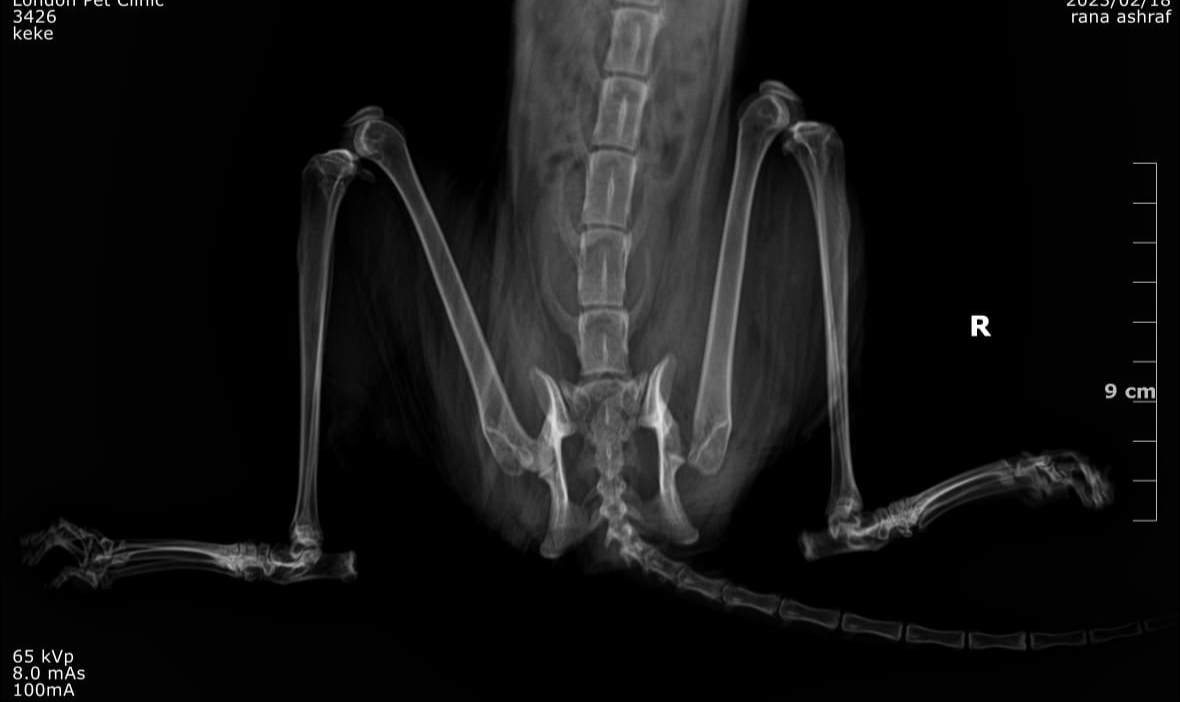

Femoral Head Ostectomy

Femoral Head and Neck Ostectomy (FHO) is a salvage surgical procedure performed to eliminate pain and restore functional limb use in animals suffering from severe hip joint

disease

The surgery involves removing the femoral head and neck, thereby eliminating bone-to-bone contact and allowing a fibrous pseudoarthrosis (“false joint”) to form

This procedure is particularly suitable for cats and small dogs, as their lighter body weight

allows excellent functional recovery postoperatively

In cats, particularly lightweight breeds such as the Scottish Shorthair, FHO yields excellent outcomes, even in bilateral cases of hip dysplasia

A 1.5-year-old male Scottish Shorthair cat was presented to the clinic with a history of progressive hindlimb lameness and difficulty jumping.

The owner reported that since early age, the cat had shown stiff movement, reluctance to climb, and occasional vocalization when handled.

No history of trauma was noted. The condition gradually worsened, affecting both hindlimbs mor severe in the right hind limb

• Bilateral hindlimb lameness with a “bunny-hopping” gait pattern

• Pain and crepitus upon hip manipulation

• Positive Ortolani sign confirming hip joint laxity

• Normal neurological function

Bilateral FHO was recommended starting with the right most affected limb and the other to be scheduled after 2 months